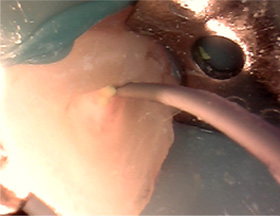

1년전 다른 치과에서 보철치료를 받은 부위에 지속적인 통증과 잇몸 염증으로 내원, 기존 보철물 수복시 신경관을 제대로 치료하지 못하여 염증이

재발된 상황이었습니다. 고운미소에서는 기존 포스트를 제거하고 오염된 부위에 약재를 삽입하여 염증을 제거하는 신경치료를 시행하였습니다.

기존 포스트 제거 후 근관내 약재 삽입